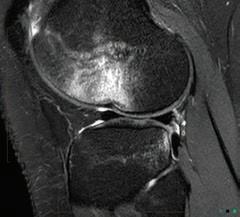

the line? Dr David Colvin 52 Imaging of the knee Dr Gavin Watson 55 Shoulder instability surgery: do it right, do it once Dr William Blakeney 61 A new health paradigm Dr

This magazine has been printed using solar electricity, and the paper is manufactured with elemental chlorine-free pulps. Both printer and paper manufacturer are certified to ISO 14001, the world’s highest environmental standard. 6 Gestational diabetes is serious Dr Emily Gianatti 39 Rule change around medical abortion Dr Alison Creagh 41 Students want more GP time Sarah Bresnehan 60 Brain aneurysms Dr Ruchi Kabra Environment ISO 14001 57 Resurfacing hip joints A/Prof Piers Yates